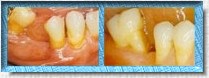

EN ESTE DIBUJO SE

APRECIA LA MIGRACIÓN DE DIENTES VECINOS ASÍ COMO DEL ANTAGONISTA

SUPERIOR OCASIONADO APIÑAMIENTO Y LA PRESENCIA DE CARIES EN CARAS

LATERALES DONDE EL CEPILLO DENTAL NO ACCEDE... EL PROBLEMA APENAS

INICIA! |

DESPUÉS DE CICATRIZAR

LA HERIDA SE COLOCO UN PUENTE FIJO PARA SUSTITUIR LA PIEZA PERDIDA

CON LO QUE SE EVITARON LAS COMPLICACIONES ANTES SEÑALADAS.